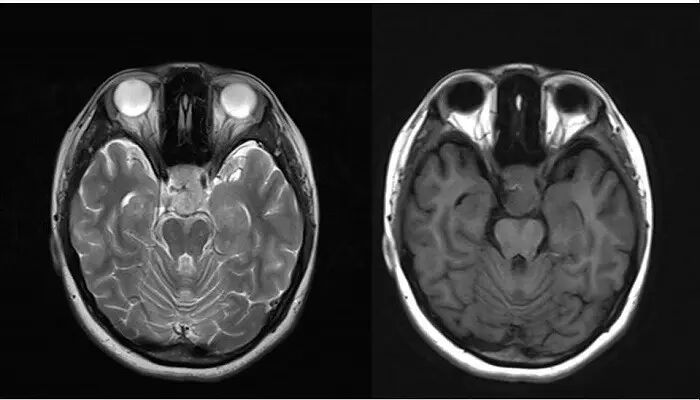

2.MR检查显示肿瘤位于鞍区,分叶状生长,呈稍长T2、稍长T1异常信号影,边界清楚,内部信号不均匀,其内可见“微囊”状异常信号影,视交叉受压上抬,DWI呈等或略高信号影,注药后呈不均匀明显强化;

3.CT检查显示肿瘤呈等密度影,可见鞍背骨质破坏;